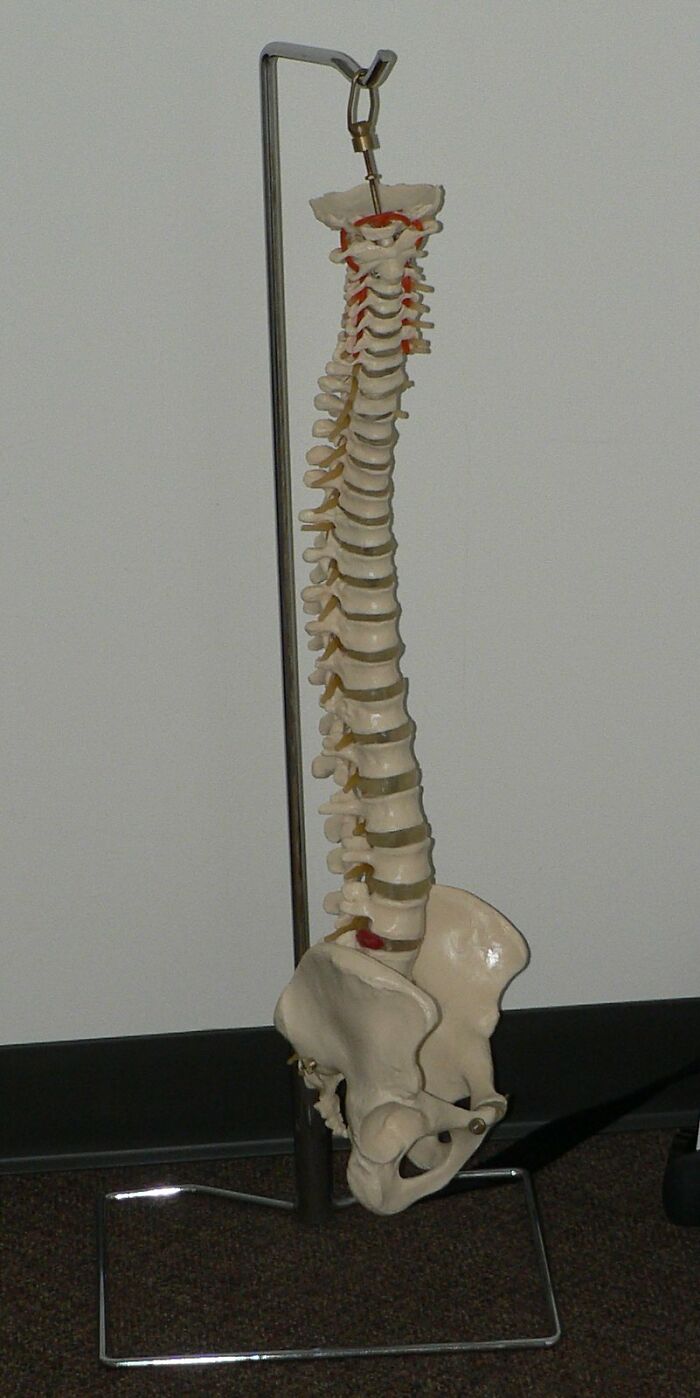

One of my ribs is not connected to my spine

all80_000_000fingers , Rick Kimpel Report